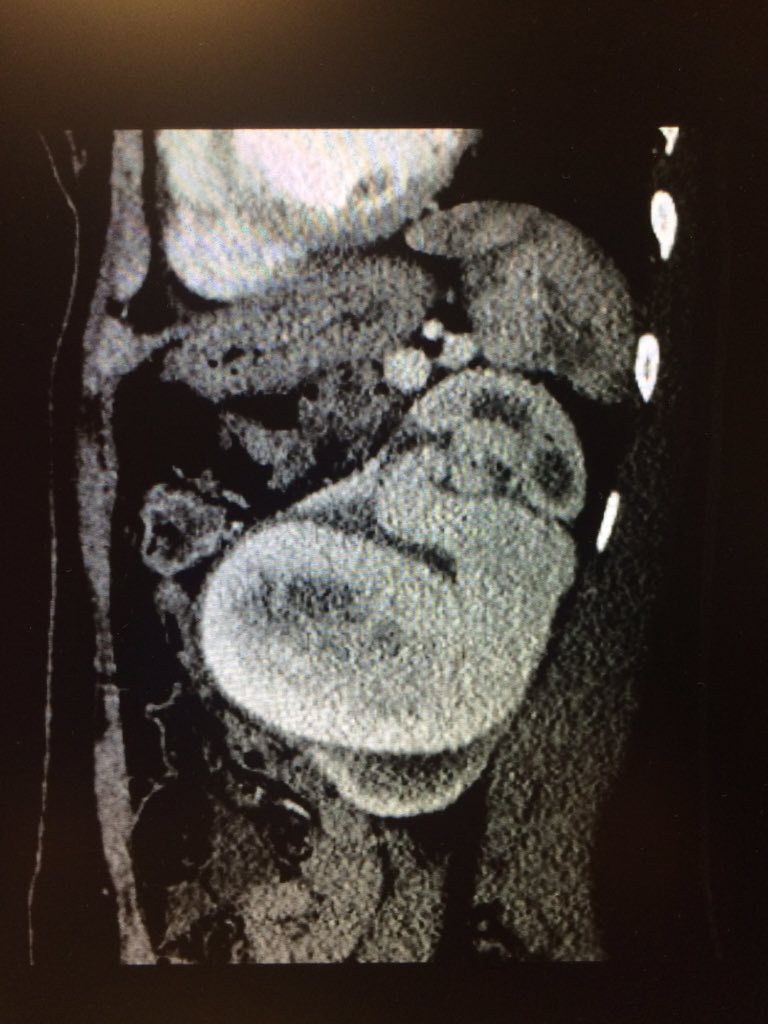

47 yo p/w massive PE s/p systemic tPA and persistent hypotension. Extensive right-sided PE on angio. Thrombus completely removed with FlowTriever mechanical thrombectomy. PA pressure decreased to 30mmHg from 64 mmHg immediately. #IRad @SIRspecialists @SIRRFS @SIR_ECS @JVIRmedia